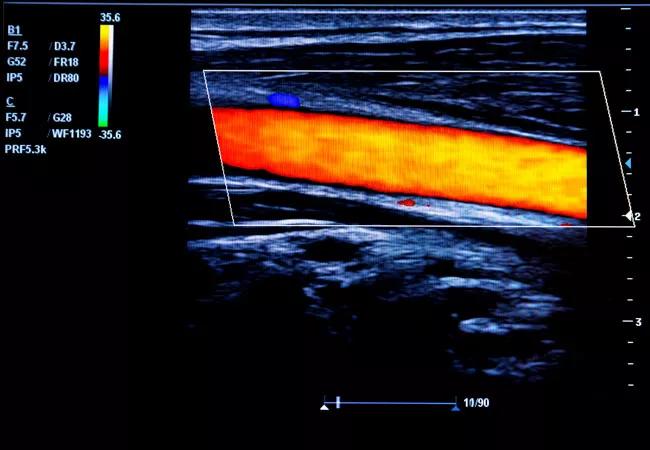

Ultrasound image of the carotid artery

Photo: Ultrasound image of the carotid artery. CASM will create three-dimensional reconstructions of plaques found in ultrasonic images like these.

Currently, carotid artery plaque composition is determined using magnetic resonance imaging, which can be costly and is not always available. With this grant, the researchers will investigate the combined power of ultrasound together with a new machine learning algorithm to better, and noninvasively, assess plaque composition.

In this study, 1,500 patients with carotid artery stenosis from Cleveland Clinic and the Louis Stokes Cleveland Veterans Affairs Medical Center will undergo ultrasound of their carotid arteries. In tandem, a new program called the Compositional Analysis System by Machine (CASM) learning algorithm will create three-dimensional reconstructions of the plaques. The investigators will test the CASM algorithm’s ability to accurately determine the degree of stenosis and predict the precise plaque composition.